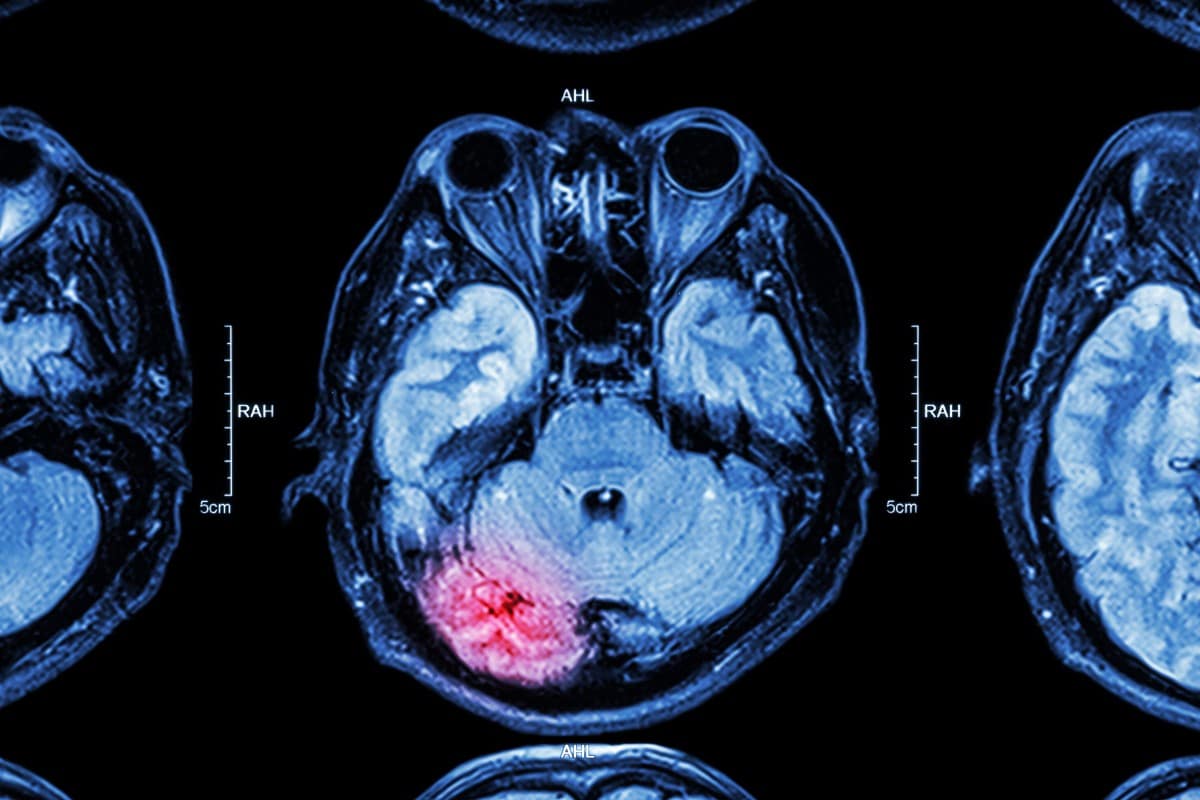

दिमागको झिल्ली बाहिर चोट लागेमा त्यो एक्स्ट्राड्युरल हेमाटोमा हो । भित्र भएमा सबड्युरल हेमाटोमा भनिन्छ । यसलाई रगत जमाउने हेमाटोमा पनि भनिन्छ । गिदीमा चोट लागेर थिलथिलो भएमा त्यसलाई कन्ट्युजन भनिन्छ । वास्तवमा ब्रेन सामान्य पिठोको डल्लो जस्तै हुन्छ । तर त्यसमा माइक्रोस्कोपिक रूपमा धेरै तारहरू हुन्छन् । चोट लाग्दा ति तार (एक्जन) हल्लिएमा डिफ्युजन एक्जोनल इन्जुरी हुने गर्छ ।

टाउकोमा चोट लागेर रगत जम्ने समस्या प्राइमरी ब्रेन इन्जुरी हो । रगत जमेपछि दिमागलाई थिच्दै मस्तिष्कमा अक्सिजन नपुग्ने समस्या सेकेन्डरी हो । चोटले ब्रेनलाई असर नगरोस् भनेर प्रि हस्पिटल केयर कन्सेप्टको अभ्यास पनि चल्तीमा छ । टाउकोमा लाग्ने सामान्य समस्यालाई कन्कसन भनिन्छ । यसले मस्तिष्कलाई हानी पुर्याउँदैन । कतिपयलाई ‘सर्ट टर्म मेमोरी लस’ हुनसक्छ । यसमा चोट लाग्नुभन्दा पहिला वा पछिका घटनाको याद रहँदैन ।